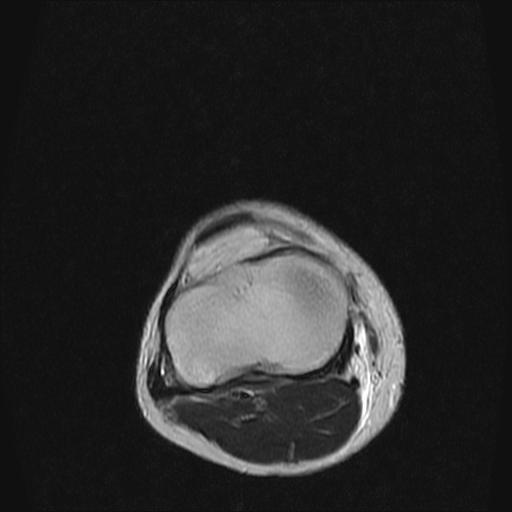

标题: MRI1265:男性40岁,右膝关节 [打印本页]

标题: MRI1265:男性40岁,右膝关节

40岁男性,右膝关节外伤,x光平片示,髁间隆突撕脱骨折。

1、前交叉韧带撕裂;

2、外侧半月板后角撕裂;

3、关节腔积液。

半月板1-2级损伤   前交叉韧带撕裂伤   关节腔少量积液  诸骨未见新鲜外伤性改变

髁间隆突撕脱骨折;内侧副韧带损伤。

内侧副韧带撕裂及关节腔积液是肯定的,但是前交叉撕裂确定吗?会不会有容积效应的因素,因为前一张前交叉显示清楚,连续性良好,且较光滑。请问楼主有关节镜支持吗?我们医院也经常有这样的患者,但苦于没有关节镜,而无法对照、证实(除非完全断裂),出现了不同的诊断结果只能毫无意义的争论。

除了关节积液外并无韧带撕裂,acl胫侧附着点有2束,正常情况下脂肪信号。此病例应加做压脂像以便观察是否有骨损伤。